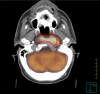

Background: Positron emission tomography (PET) has a potential improvement for staging and radiation treatment planning of various tumor sites. We analyzed the use of 18F-fluorodeoxyglucose (FDG)-PET/computed tomography (CT) images for staging and target volume delineation of patients with head and neck carcinoma candidates for radiotherapy.

Methods: Twenty-two patients candidates for primary radiotherapy, who did not receive any curative surgery, underwent both CT and PET/CT simulation. Gross Tumor Volume (GTV) was contoured on CT (CT-GTV), PET (PET-GTV), and PET/CT images (PET/CT-GTV). The resulting volumes were analyzed and compared.

Results: Based on PET/CT, changes in TNM categories and clinical stage occurred in 5/22 cases (22%). The difference between CT-GTV and PET-GTV was not statistically significant (p = 0.2) whereas the difference between the composite volume (PET/CT-GTV) and CT-GTV was statistically significant (p < 0.0001).

Conclusion: PET/CT fusion images could have a potential impact on both tumor staging and treatment planning.